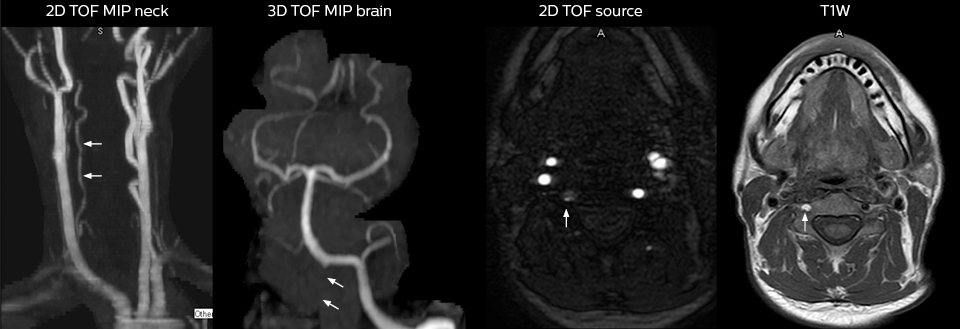

“We use mDIXON TSE extensively in our spine imaging in the emergency room,” says Dr. Karis. “It’s particularly nice in that it is very robust with regard to susceptibility type of problems that would come up with traditional spectral fat-saturated images; these problems are essentially eliminated with the mDIXON technique. In our ED environment it’s really nice to have the fat-free imaging that goes along with the mDIXON technique.

“For the thoracic and cervical spine routine non-contrast exam, for example, we perform one mDIXON T2 TSE sequence, which provides us with two outputs: the fat-and-water-together T2-weighted images, as well as the water-only sagittal T2-weighted images. And then we also perform an axial gradient echo exam.”

A range of protocol sheets was developed to help ensure that referring physicians order the most appropriate MRI exam. The optimized MRI protocols also include 3D contrast-enhanced imaging, allowing neurosurgeons to comfortably use the isotropic data in the operating room while performing stereotaxic surgery.